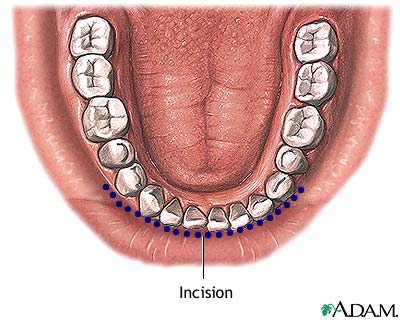

- The surgeon will make a cut inside your mouth along the lower gum. This gives the surgeon access to the chin bone.

- The surgeon uses a bone saw or chisel to make a second cut through the jaw bone. The jaw bone is moved and wired or screwed in place with a metal plate.

- The cut is closed with stitches and a bandage is applied. Because the surgery is performed inside your mouth, you will not see any scars.